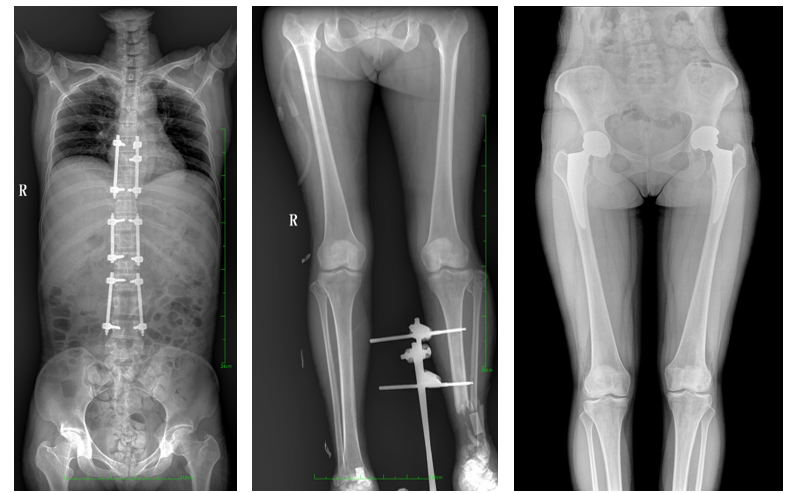

17"*34"有效視野,是市面大尺寸平板的2倍,一次成像不拼接。相較于多張攝影再軟件拼接的DR設(shè)備,PLX8600解決了拼接圖像存在密度不均勻,拼接處圖像配準(zhǔn)和放大效應(yīng)等問(wèn)題,給臨床帶來(lái)了真正的大視野影像解決方案,高清畫(huà)質(zhì),準(zhǔn)確成像不失真,可一次性覆蓋全脊柱或雙下肢影像。PLX8600大視野平板動(dòng)態(tài)DR攝影速度快,患者可以更快的完成檢查,且單次攝影輻射劑量是常規(guī)多張攝影再軟件拼接DR的1/2或1/3,低劑量給患者更多關(guān)愛(ài)。

除常規(guī)靜態(tài)攝影外,PLX8600大平板具備動(dòng)態(tài)透視和點(diǎn)片功能,透視采集功能可支持大視野、多角度的可視化觀察。通過(guò)可視化的動(dòng)態(tài)影像,配合點(diǎn)片功能,能夠很好的觀察復(fù)雜部位病灶,有效的抓取關(guān)鍵幀,降低患者多次攝片的概率,安全又高效。如:全脊柱狀態(tài)評(píng)估、長(zhǎng)骨關(guān)節(jié)活動(dòng)度、下肢靜脈造影瓣膜功能評(píng)估、消化道功能評(píng)估、脊髓造影等更多大視野臨床應(yīng)用,多面手給醫(yī)生更多驚喜。